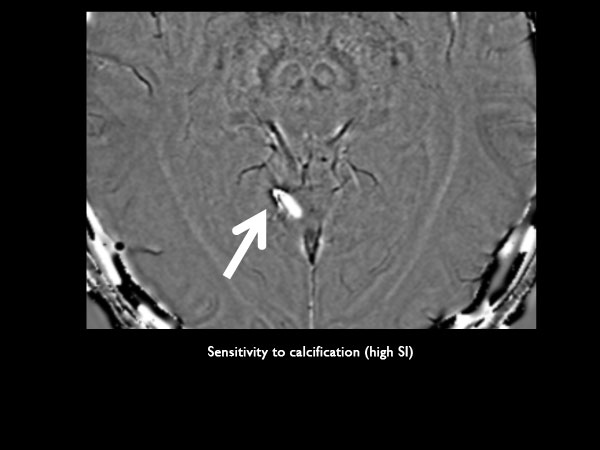

Axial SWIp (phase)